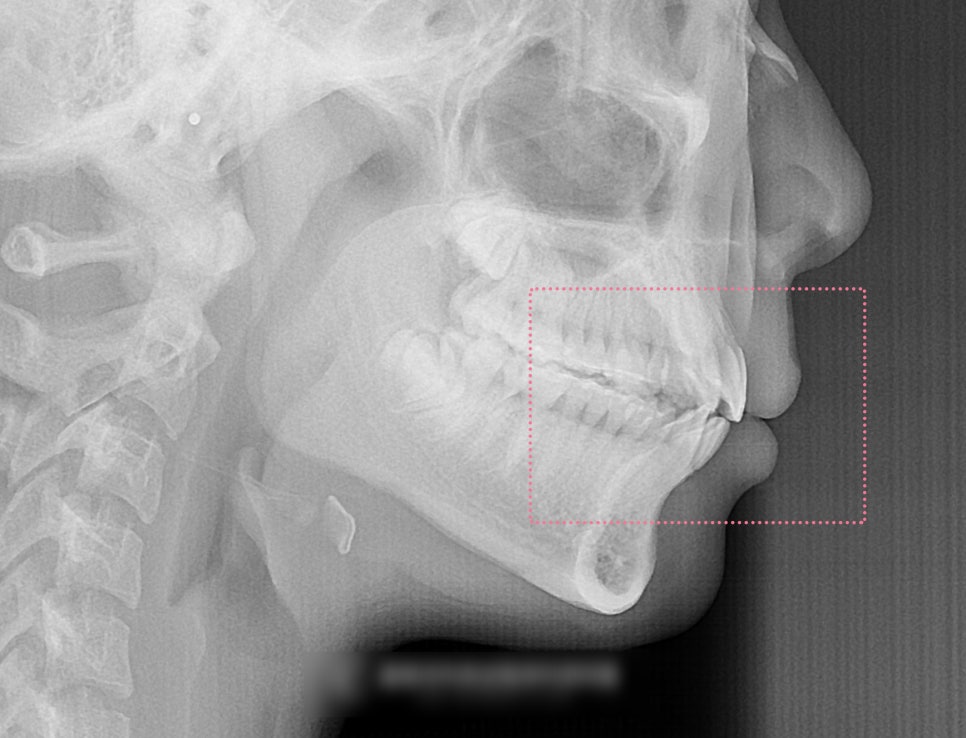

동시에, 이 환자의 경우

입술의 긴장감도 있었기에

이러한 부분들도 같이 고려를 하여

돌출입 교정을 진행하기로 했습니다.

다만, 돌출입 교정의 경우

리케츠 라인(심미선)을 기준으로

입술이 바깥쪽에 나와 있다면

발치 결정을 내릴 가능성이 높습니다.

따라서 이 환자의 경우,

앞니를 가지런하게는 할 수 있으나

입술의 긴장감까지 같이 개선을

요했기 때문에 소구치 4개의 발치는

진행하기로 했습니다.